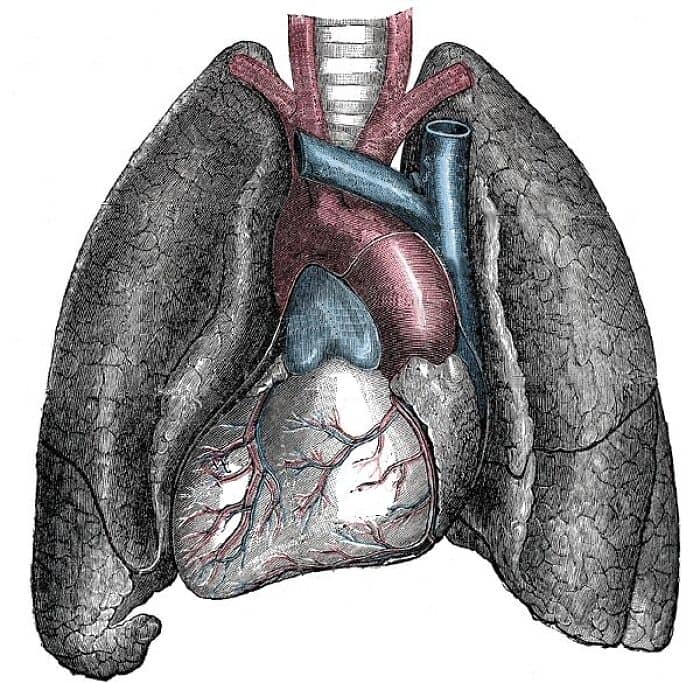

In my anatomy lab, my groups’s cadaver had died from systemic complications of stage 4 lung cancer and when we got to the lungs they were two rock hard, necrotic blackened masses that looked nothing like the other cadaver’s pink and spongy lungs.

My anatomy prof took one lung out and wrung it resulting in this putrid black goo flowing out of the lung.

As he was draining the lung, he mentioned in an Indian accent

“This. This is what happens when you smoke”.